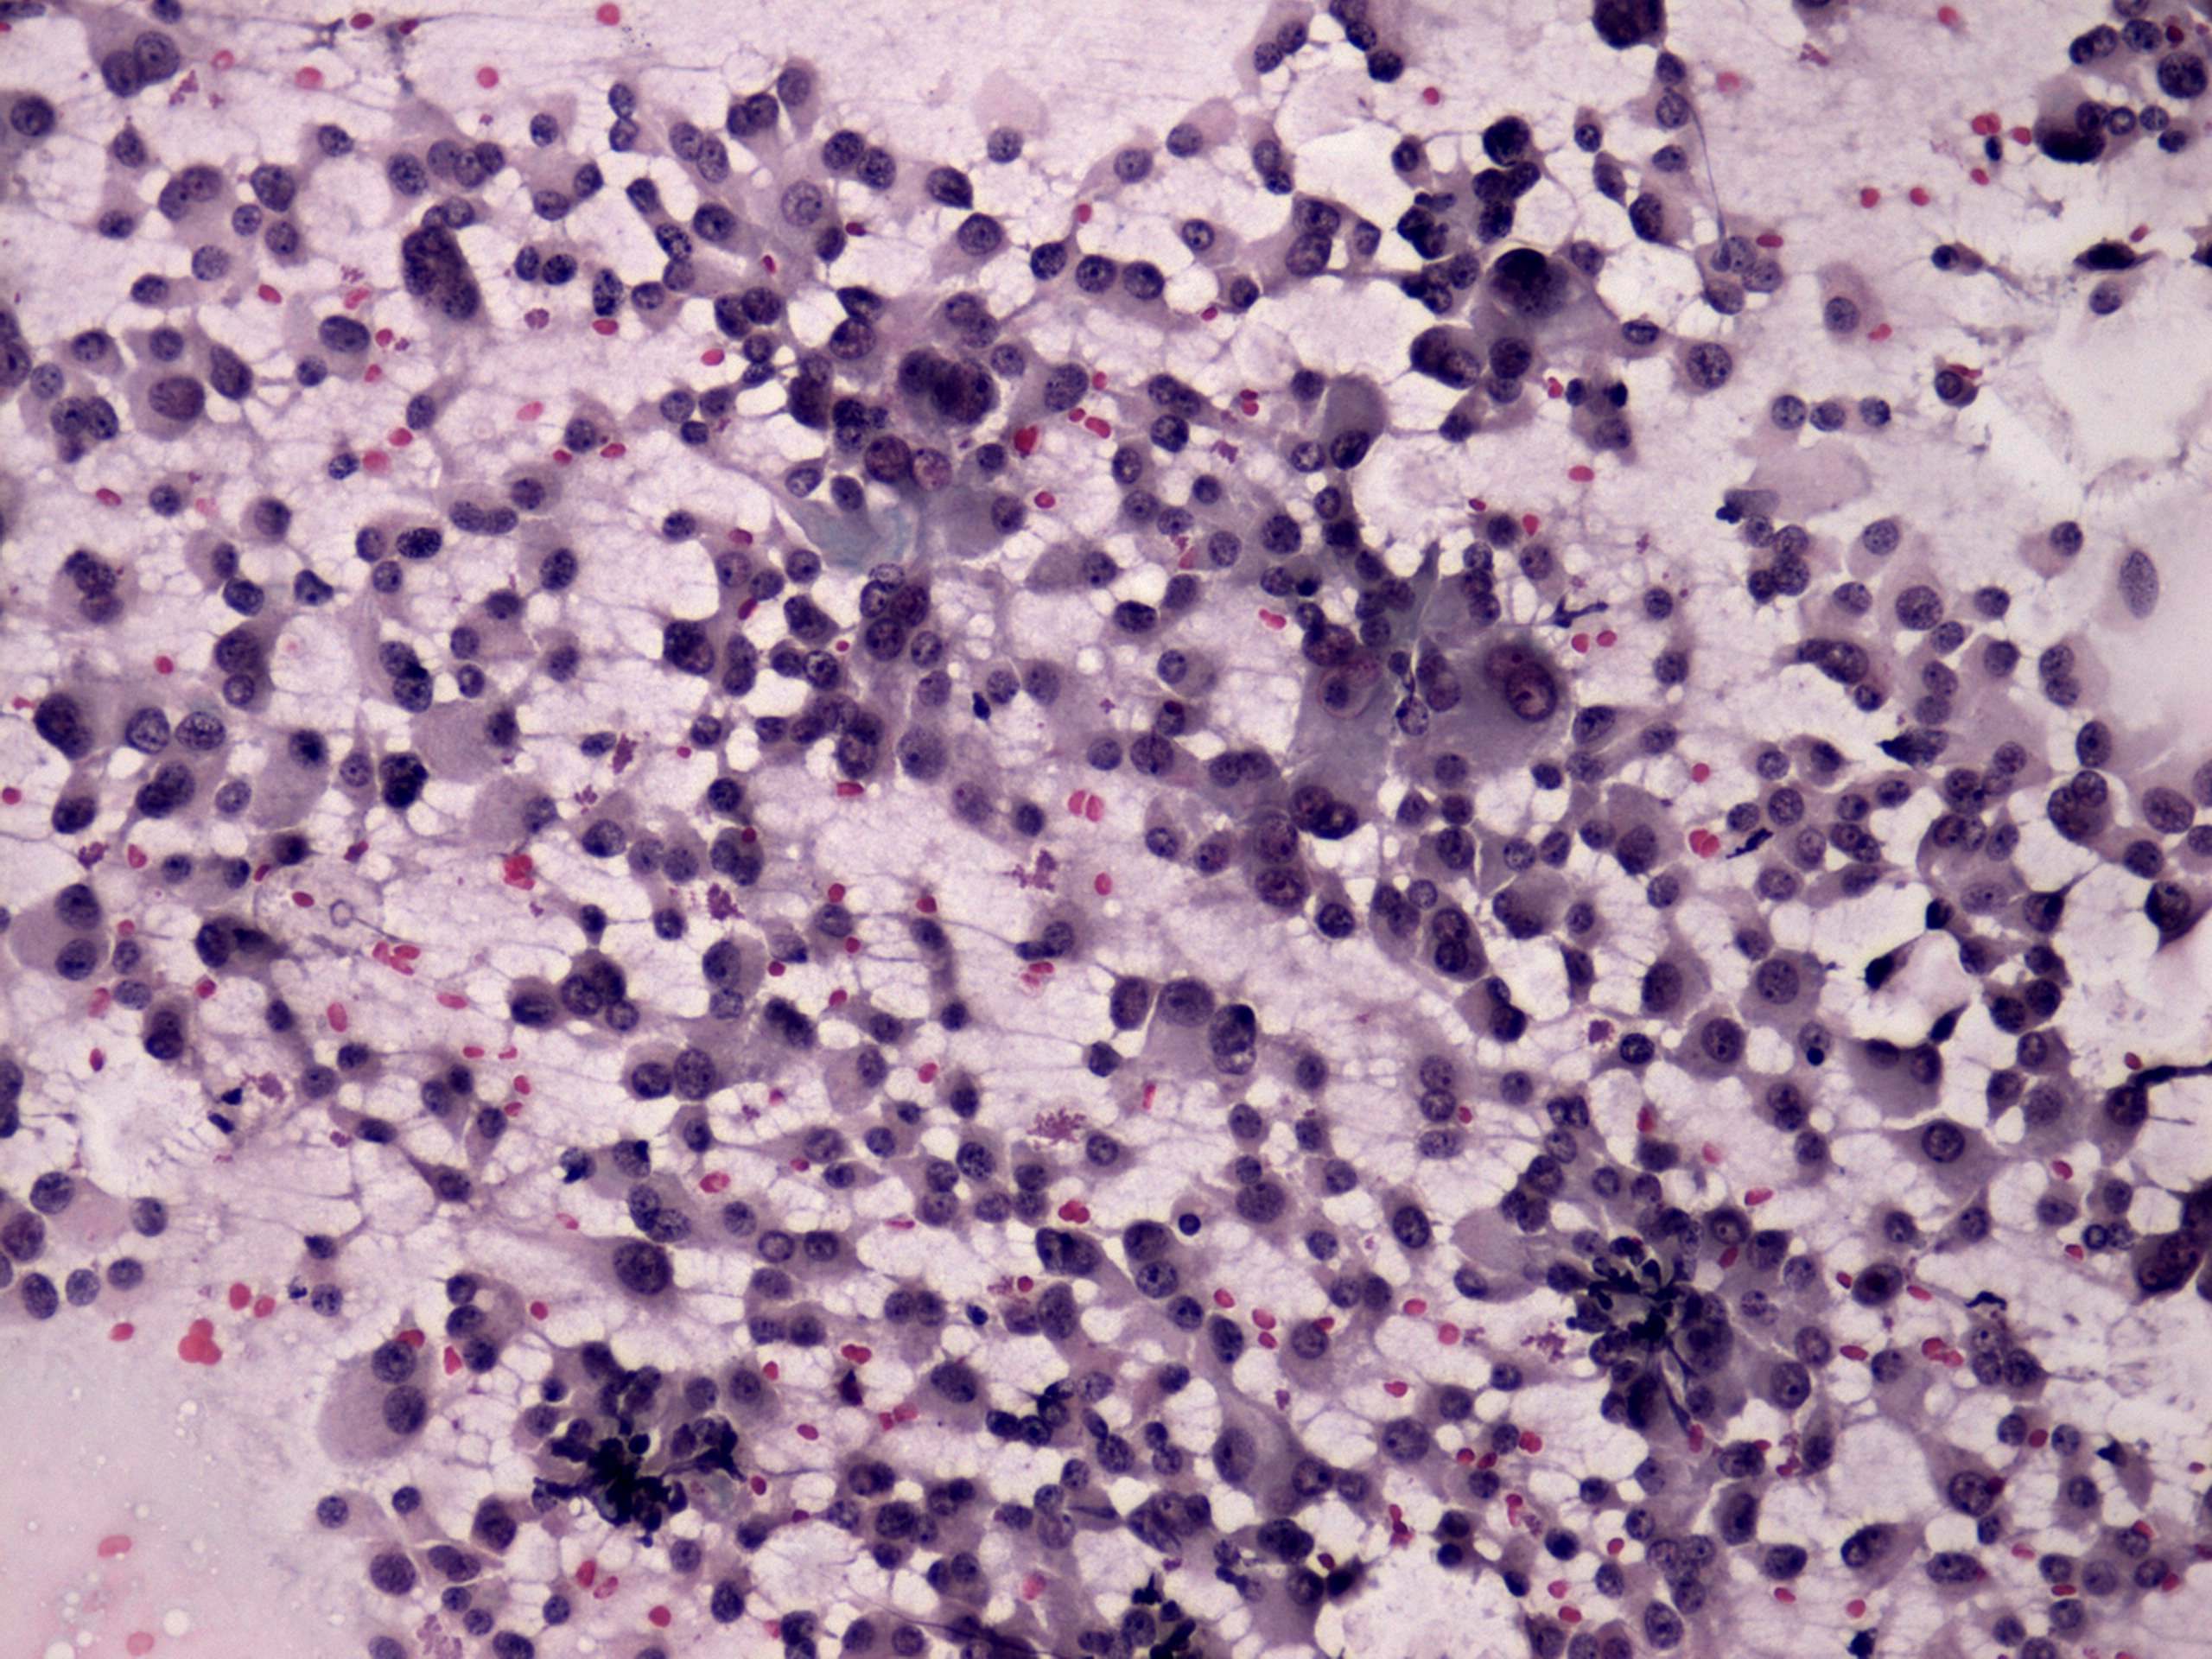

Thyroid cancers - case 529 (cytologic picture 2)

Pap-smear, 200x. There are several multinucleated tumor cells.